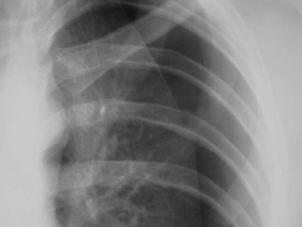

Pneumotorace simplu stang Pneumotorace

simplu stang

Pneumotorace